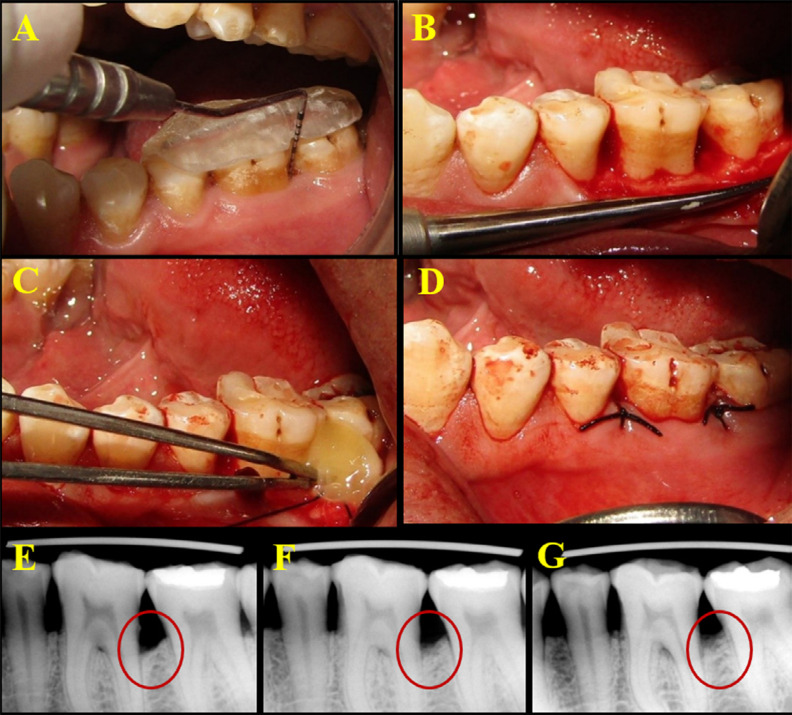

Methodology: This study included 17 patients of both sexes (12 men, 5 women) aged 30-55 years (mean age = 37.7±4.4 years) who fulfilled the inclusion criteria (radiographic and clinical evaluation for bilateral IOD with probing pocket depth (PPD ≥ 6 mm). A split-mouth design was used in each patient. A total of 34 sites in the mandibular arch randomly received PRFM alone + open flap debridement (OFD) [Control sites] or supercell (PRFM+PBMSCs) + OFD [Test sites]. The clinical parameters plaque index (PI), gingival index (GI), PPD, clinical attachment level (CAL), and in the radiographic parameters; defect depth (DD) and defect fill percentage (DFP) were recorded at baseline, 3 and 6 months postoperatively. Early wound healing index (EHI) was used at 1 week to assess wound healing ability.

Results: At 6 months, radiographic parameters revealed significant reduction in DD (P<0.001) and significant DFP values in the test group compared with the control group. The supercell showed significant improvement in PPD and CAL at the end of 6 months (P<0.001). EHI scores at 1 week showed no statistically significant difference between the test and control groups.